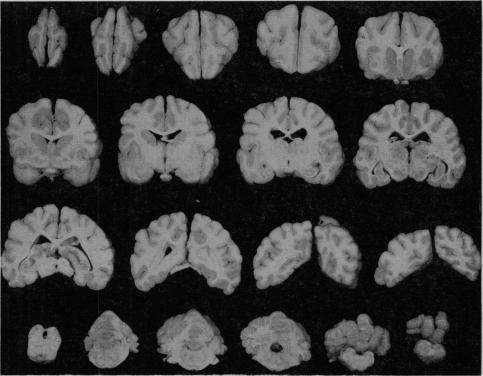

https://cdn.ncbi.nlm.nih.gov/pmc/blobs/f88e/1888895/05522a714d2c/procrsmed00382-0088-a.jpg